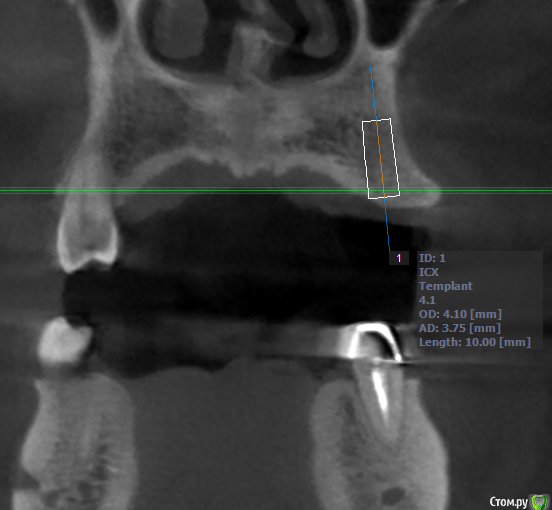

Evikrol Опубликовано 16 мая, 2018 Поделиться Опубликовано 16 мая, 2018 Я бы вот так поставил и подлиннее и на винтовую 5 Ссылка на комментарий